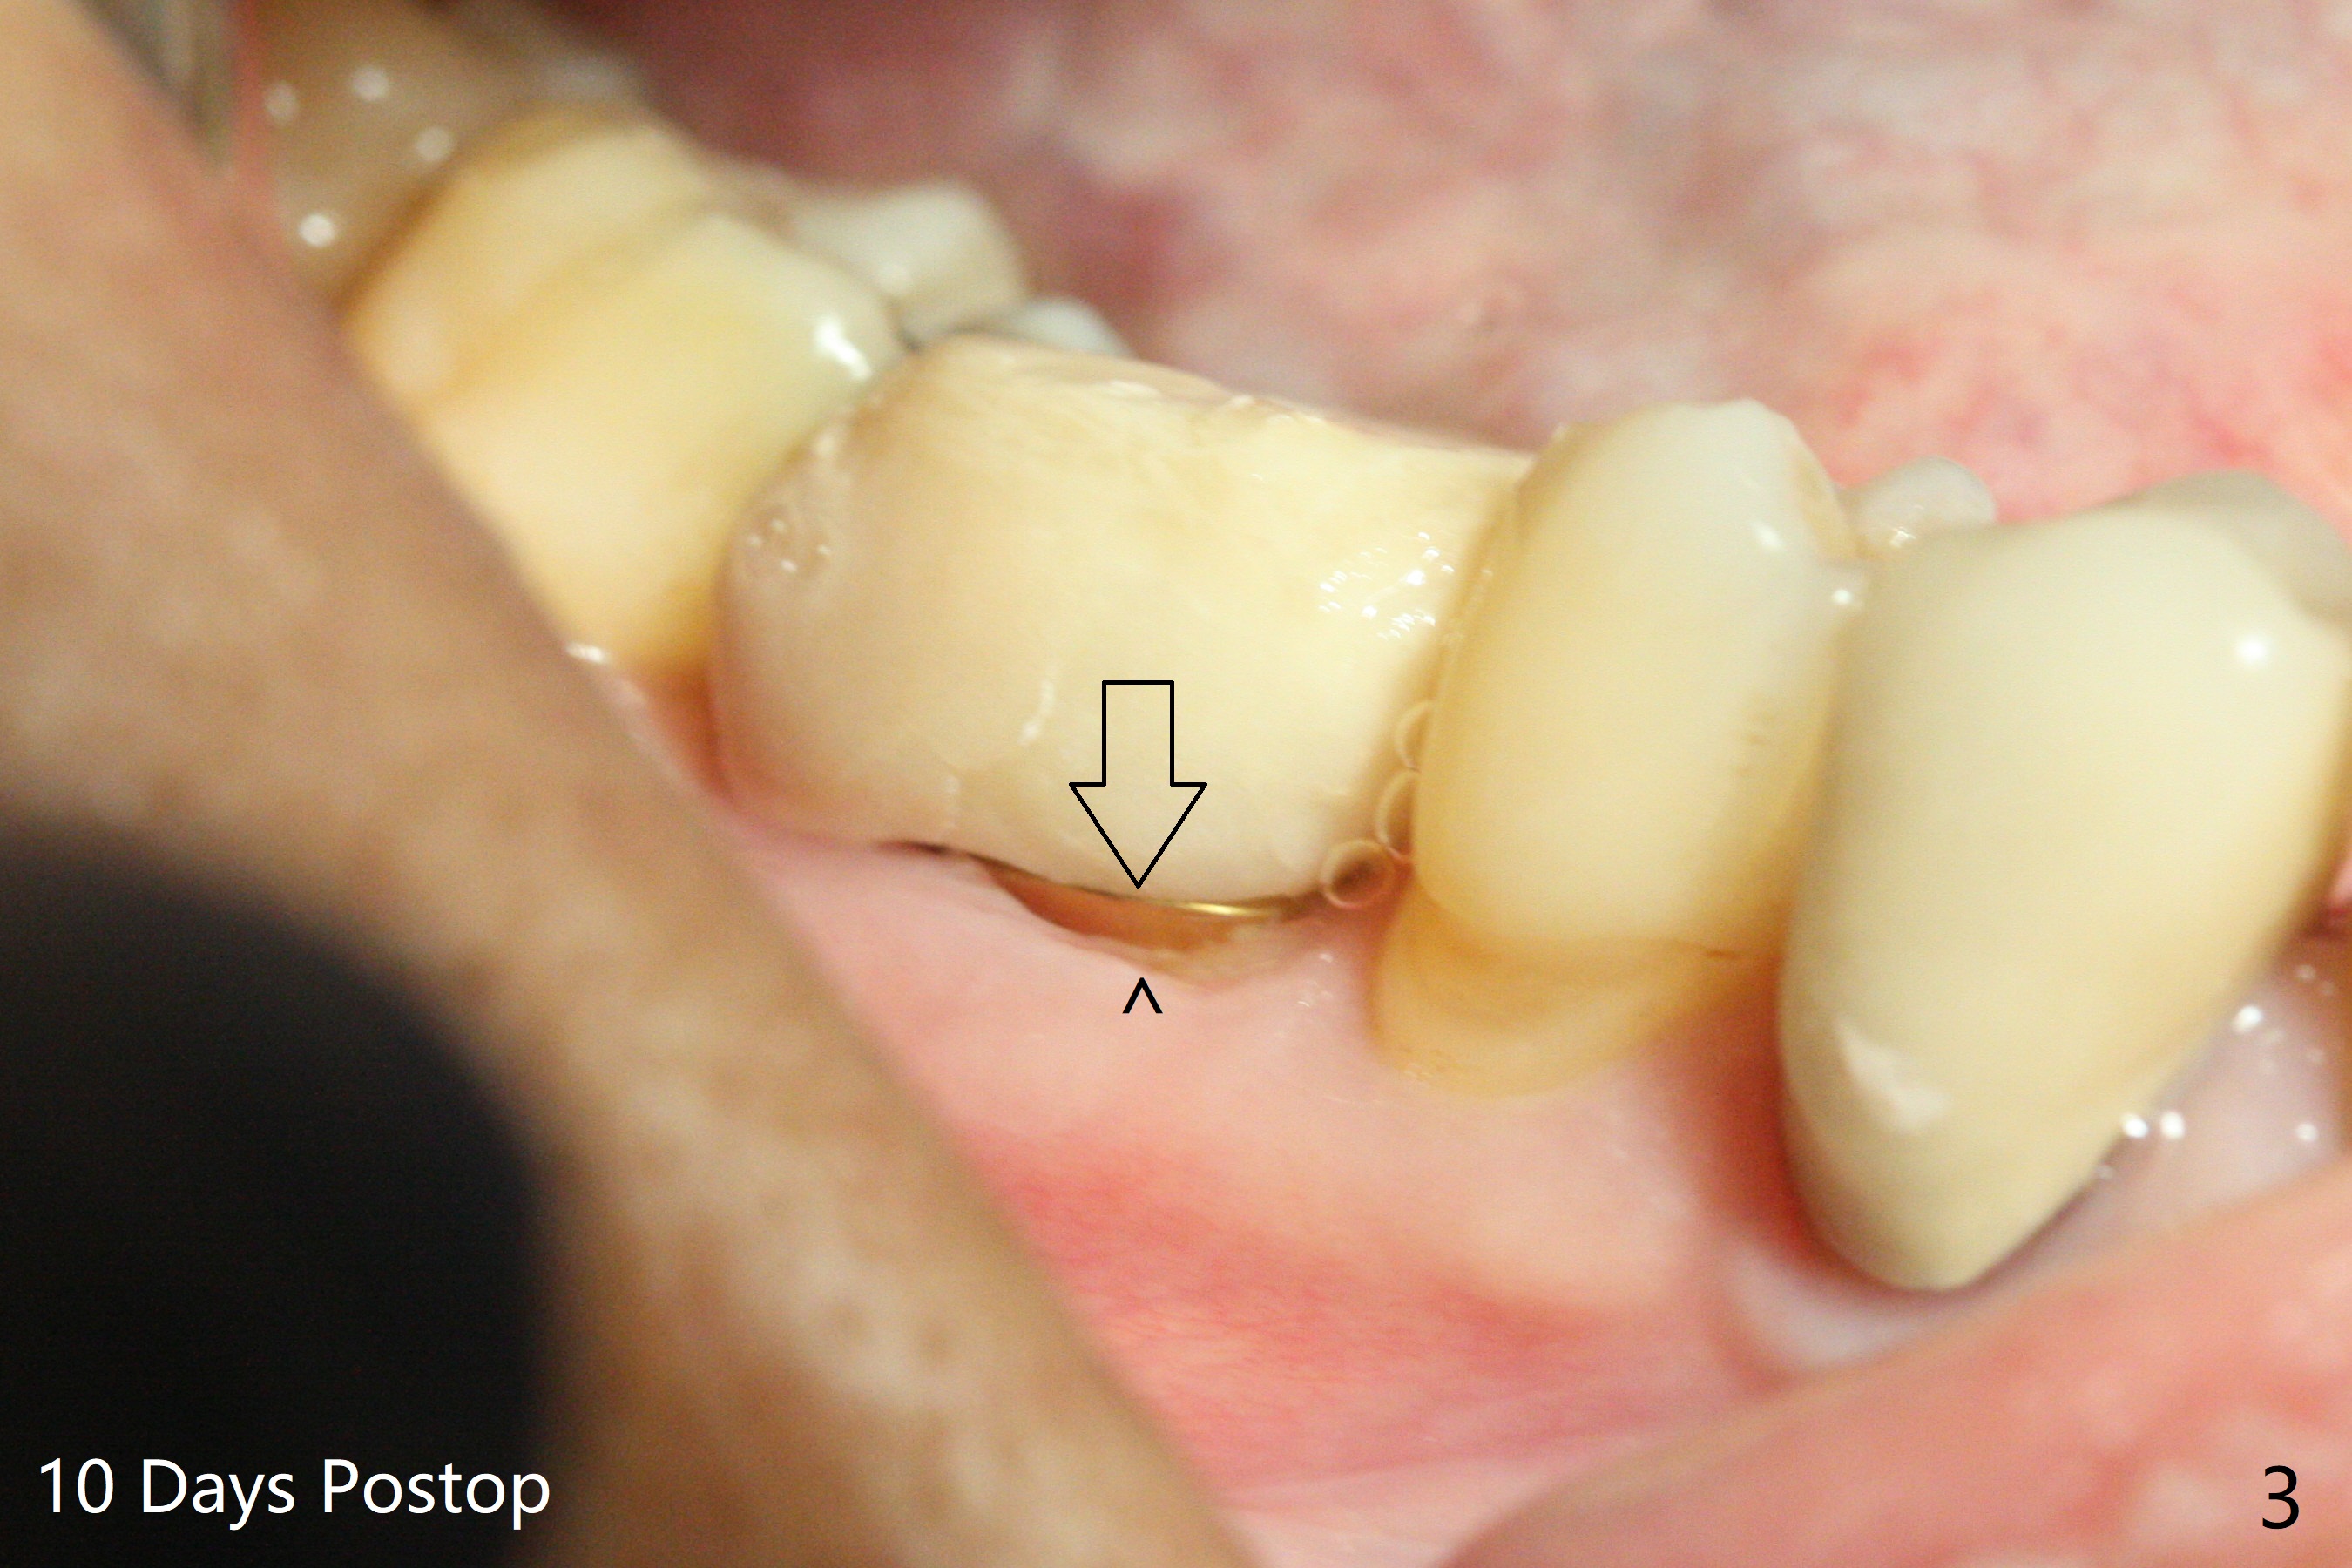

In spite of severe bone loss and 1.86 mm remaining bone after extraction of the tooth #30, a 5x7.3 mm implant achieves insertion torque of 35 Ncm with an immediate provisional (Fig.1). Periodontal dressing is applied for additional fixation of the bone graft (*) and Osteogen plug (P). Although the implant is placed in the mesial socket, the coronal end of the abutment is in the middle of the edentulous area. The patient is extremely pleased with no pain surgery. There is no postop paresthesia. The periodontal dressing (Fig.2 D) remains in place and buccal to the temporary crown (T) 10 days postop. When the former is removed, there is a gap between the margin of the provisional and that of the gingiva (Fig.3 between arrow and arrowhead), suggesting that the latter has shrunk postop. If there were no periodontal dressing, some of bone graft may have been lost. The distal socket heals when the immediate provisional is removed for revision 5 weeks postop (Fig.4). With gingival retraction cords, the abutment margin is prepared 2 months postop, particularly distal, to reduce food impaction in the future. If there is no abutment screw loosening with final restoration, it suggests that computer designed trajectory is acceptable. The implant plateau seems to be covered by the bone 4.5 months postop (Fig.5). In fact the mesiobuccal margin of the abutment is close to the corresponding crestal bone. The gingiva looks healthy 5 months postop (immediately before cementation, Fig.6), although MO amalgam of the tooth #31 is breaking down (*). Return to Lower Molar Immediate Implant, Prevent Molar Periimplantitis (Protocols, Table), Trajectory Xin Wei, DDS, PhD, MS 1st edition 04/17/2019, last revision 09/14/2019